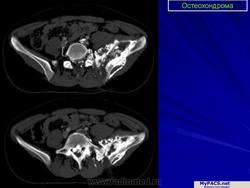

Остеохондрома (костно-хрящевой экзостоз). Это доброкачественный грибовидный отросток, соединенный с помощью костной ножки с подлежащим метафизом. Головка этого грибовидного образования покрыта хрящом. Остеохондрома бывает одиночной и множественной. Последний вариант относится к множественному наследственному экзостозу, который наследуется по аутосомно-доминантному типу. Полагают, что одиночная остеохондрома возникает из-за смещения боковой порции ростковой зоны, которая затем пролиферирует в косом направлении по отношению к оси кости и в направлении от ближайшего сустава. Как правило, такая опухоль обнаруживается в позднем юношеском возрасте или у молодых взрослых лиц (в то время как множественные остеохондромы определяются уже в детстве). По неизвестным причинам мужчины поражаются в 3 раза чаще женщин. Остеохондрома обычно растет от метафиза, локализуясь рядом с ростовой пластинкой длинных трубчатых костей. Иногда опухоль развивается из костей таза, лопаток, ребер. При локализации в указанных губчатых костях остеохондрома, как правило, имеет короткую ножку. Наконец, совсем редко эта опухоль поражает короткие трубчатые кости кистей и стоп.

Остеохондрома - медленно растущее новообразование. При вовлечении в зону ее роста нерва или при переломе ножки опухоли отмечают болезненность. Но часто остеохондрому обнаруживают как случайную находку. При множественных наследственных экзостозах подлежащие кости могут быть искривлены и укорочены, что отражает генетическое нарушение роста эпифизов. В периоде закрытия ростковых пластинок рост остеохондромы обычно прекращается. Однако некоторые ее варианты все же продолжают расти в течение детства пациента. Большинство остеохондром отличается совершенно «безобидным» клиническим поведением. Лишь менее 1 % таких опухолей способны превращаться в хондросаркомы или какие-либо другие саркомы [по Cotran R.S., Kumar V., Collins Т., 1998]. Причем риск малигнизации существенно выше у лиц с наследственным вариантом остеохондромы.

Строение остеохондромы весьма характерно. Опухоль имеет грибовидную форму, ее размеры варьируют в пределах 1-20 см. Наружный слой головки этого новообразования покрыт различной толщины доброкачественным гиалиновым хрящом, ограниченным надхрящницей. Хрящ имеет вид дезорганизованной ростовой пластинки. Оп подвергается энхондральной оссификации, а вновь образованная кость формируется во внутренних частях головки и ножки. Корковый слой ножки опухоли сливается с аналогичным слоем диафиза кости, а костномозговые полости остеохондромы и самой кости сообщаются между собой.

Остеохондрома.